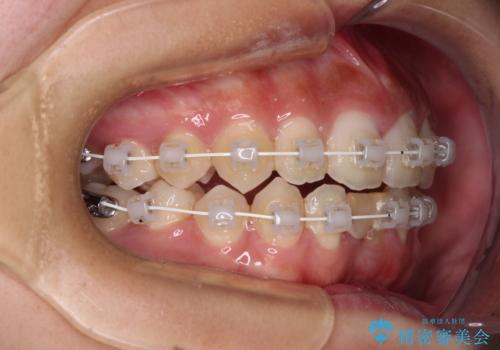

- 矯正装置

- 審美装置

ワイヤー装置により矯正治療を行うとともに舌突出癖改善のためのトレーニングをしっかりと行っていただき、咬み合わせが安定した位置となったタイミングで下顎前歯にブリッジの仮歯を装着していく計画としました。

矯正治療終了後に速やかにオールセラミックブリッジを装着していくこととしました。